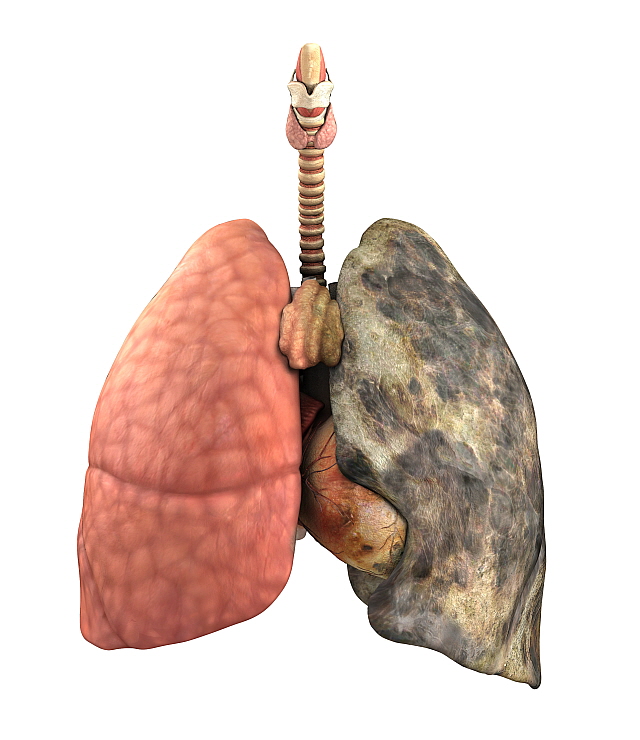

폐렴 증상 3. 호흡 곤란 및 숨 가쁨

폐에 염증이 생기면 산소 교환이 어려워져

숨이 차고 가슴이 조이는 느낌,

또는 평소보다 가쁜 숨, 짧은 호흡이 나타날 수 있어요.

계단을 오르거나 평소보다 조금만 움직여도 숨이 찰 수 있습니다.4. 흉통(가슴 통증)